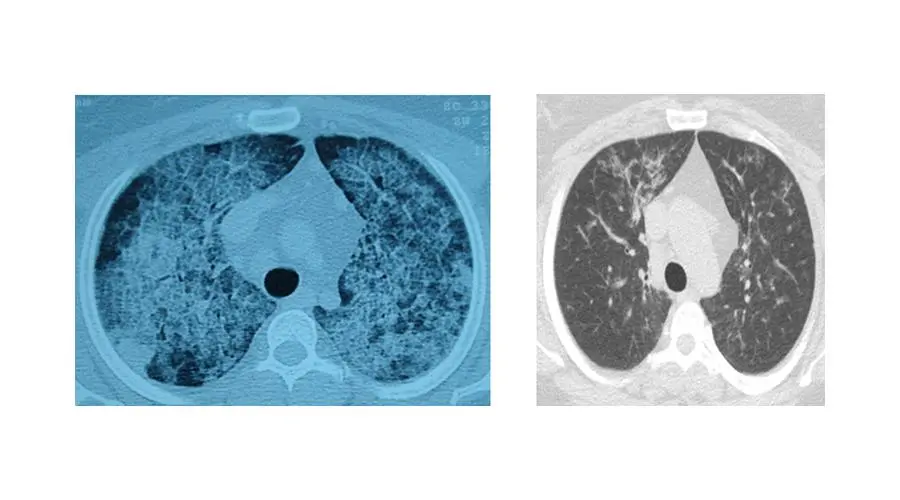

Uzmanlar, bu hastalığın akciğerlerdeki hava keseciklerinde kişinin kendi yağ ve proteinlerinin birikmesi sonucu geliştiğini, belirtiler arasında nefes darlığı, aşırı halsizlik ve yorgunluğun bulunduğunu belirtiyor. Çoğu zaman astımla karıştırılan hastalık, ancak ileri tetkiklerle kesin olarak teşhis edilebiliyor.

Sadece deneyimli merkezlerde uygulanabilen akciğer yıkamasının, ameliyathane koşullarında, hastanın uyutularak her seansta 15-20 litre steril su verilmesi ve geri alınması yöntemiyle yapıldığını anlatan Ergur, şunları kaydetti: